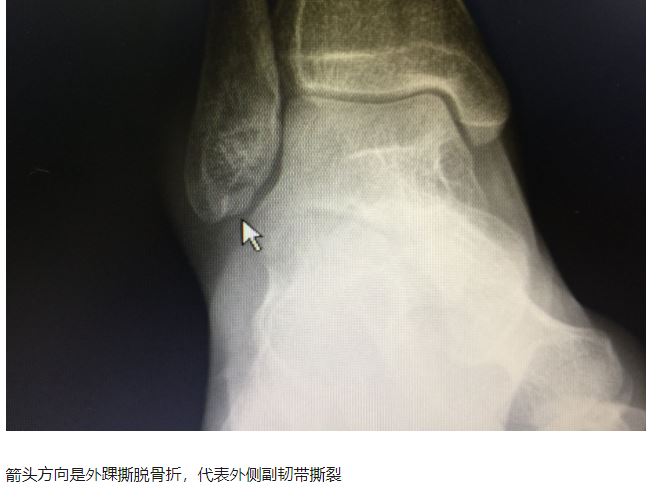

还有一种比较特殊的:撕脱骨折,是韧带完全撕裂下来的表现

踝关节扭伤,在踝在影像学仅表现为撕脱骨折,骨折块很小,既不能引起病人的重视,有时候甚至不能引起大夫的重视,但是踝关节扭伤后最容易出现损伤的就是外侧副韧带,而小小的骨折片是韧带附着点,撕脱以后高度提示韧带断裂,不重视极易引起踝关节日后慢性不稳而丧失运动能力,甚至出现创伤性关节炎,所以不能根据骨折块的大小来确定严重程度。